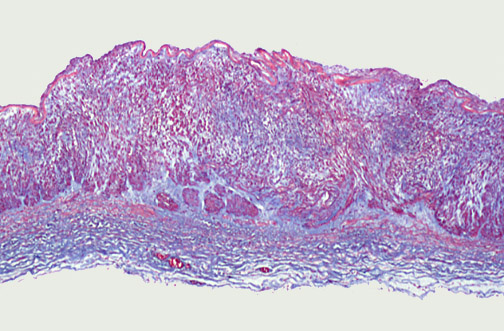

![]() | An uncommon form of vascular obstruction involving medium-sized muscular arteries is produced by fibromuscular dysplasia. In this condition, there are irregular areas of fibrous thickening, mostly involving the media, with an irregular arterial wall and focal lumenal narrowing. This process is seen here with trichrome stain at low magnification in a section through carotid artery. However, the renal arteries are most often affected, making this disease one of the surgically correctible causes for hypertension. This process is seen diagramatically below. |